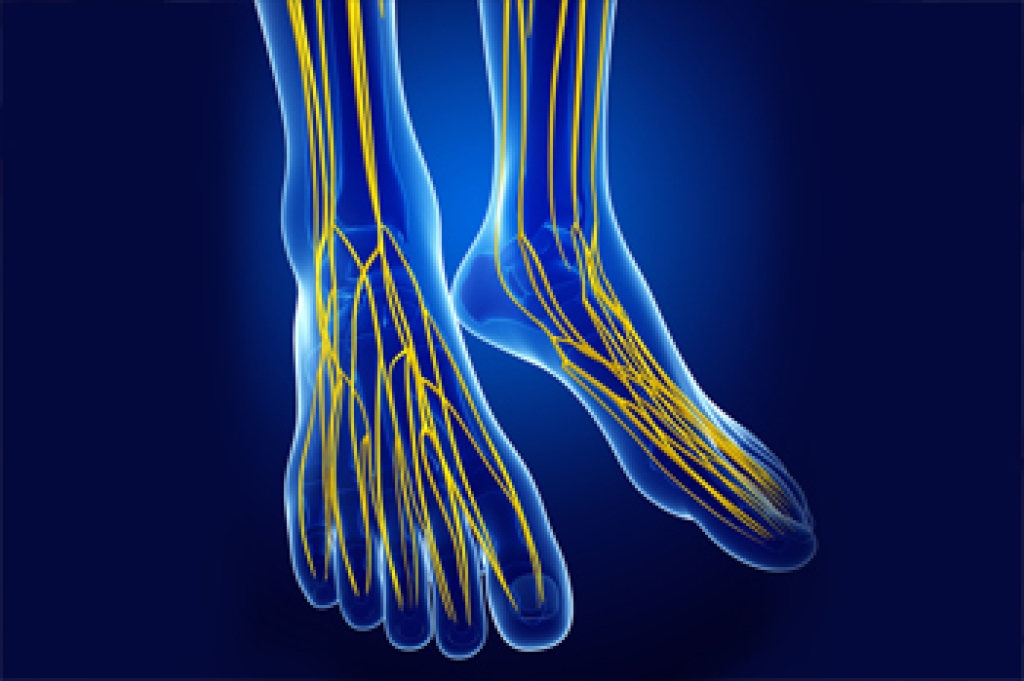

Tarsal tunnel syndrome is a nerve disorder in which the posterior tibial nerve, located near the heel of the foot, is compressed. This is usually caused by participating in repetitive activities, such as running or jumping, that put stress on the nerve and surrounding areas. However, it can also be the result of a trauma, having flat feet, or being overweight. Tarsal tunnel syndrome causes foot and ankle pain, burning, tingling, and numbness. The pain usually worsens while walking and can improve with rest. There are several treatments for tarsal tunnel syndrome, including resting and icing the affected leg, taking oral pain medications, injecting steroids into the area, immobilizing the leg, wearing an orthotic, or physical therapy. In more severe cases, surgery may be needed to decompress the posterior tibial nerve. If you are experiencing the symptoms of tarsal tunnel syndrome, please seek the care of a podiatrist.

Tarsal tunnel syndrome is a nerve disorder in which the posterior tibial nerve, located near the heel of the foot, is compressed. This is usually caused by participating in repetitive activities, such as running or jumping, that put stress on the nerve and surrounding areas. However, it can also be the result of a trauma, having flat feet, or being overweight. Tarsal tunnel syndrome causes foot and ankle pain, burning, tingling, and numbness. The pain usually worsens while walking and can improve with rest. There are several treatments for tarsal tunnel syndrome, including resting and icing the affected leg, taking oral pain medications, injecting steroids into the area, immobilizing the leg, wearing an orthotic, or physical therapy. In more severe cases, surgery may be needed to decompress the posterior tibial nerve. If you are experiencing the symptoms of tarsal tunnel syndrome, please seek the care of a podiatrist.

Tarsal tunnel syndrome can be very uncomfortable to live with. If you are experiencing tarsal tunnel syndrome, contact Kevin Powers, DPM of The Center for Lower Extremity Nerve Surgery. Our doctor can provide the care you need to keep you pain-free and on your feet.

Tarsal Tunnel Syndrome

Tarsal tunnel syndrome, which can also be called tibial nerve dysfunction, is an uncommon condition of misfiring peripheral nerves in the foot. The tibial nerve is the peripheral nerve in the leg responsible for sensation and movement of the foot and calf muscles. In tarsal tunnel syndrome, the tibial nerve is damaged, causing problems with movement and feeling in the foot of the affected leg.

Common Cause of Tarsal Tunnel Syndrome

- Involves pressure or an injury, direct pressure on the tibial nerve for an extended period of time, sometimes caused by other body structures close by or near the knee.

- Diseases that damage nerves, including diabetes, may cause tarsal tunnel syndrome.

- At times, tarsal tunnel syndrome can appear without an obvious cause in some cases.

The Effects of Tarsal Tunnel Syndrome

- Different sensations, an afflicted person may experience pain, tingling, burning or other unusual sensations in the foot of the affected leg.

- The foot muscles, toes and ankle become weaker, and curling your toes or flexing your foot can become difficult.

- If condition worsens, infections and ulcers may develop on the foot that is experiencing the syndrome.

A physical exam of the leg can help identify the presence of tarsal tunnel syndrome. Medical tests, such as a nerve biopsy, are also used to diagnose the condition. Patients may receive physical therapy and prescriptive medication. In extreme cases, some may require surgery.